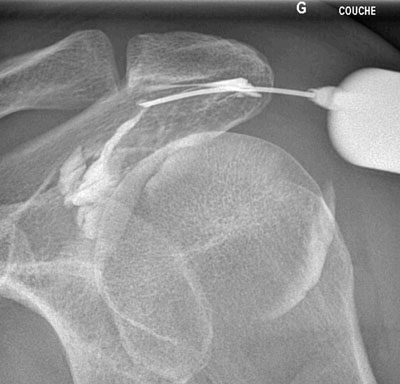

Radiographie de l'épaule. L'épaule a 2 articulations : l'articulation acromio-claviculaire (flèche pleine) et l'articulation omo-humérale (flèche creuse).

Infiltration de l'articulation omo-humérale (épaule).

Après ponction directe de l'articulation, il est injecté du produit de contraste afin de s'assurer de la position intra-articulaire de l'aiguille avant d'injecter l'anti-inflammatoire.